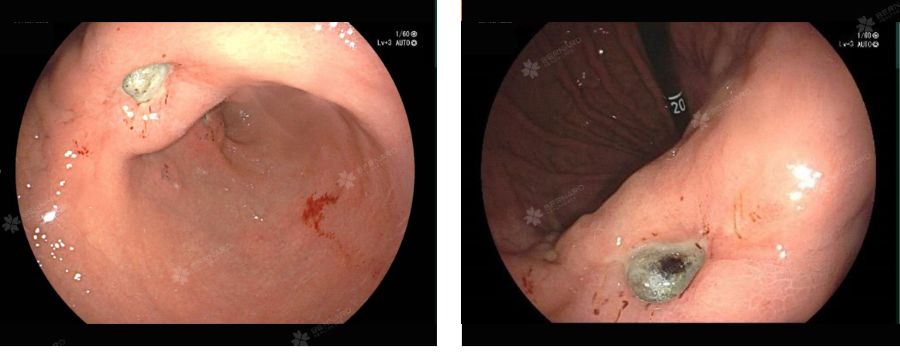

Từ hình ảnh nội soi, bác sĩ chẩn đoán xuất huyết tiêu hóa trên do loét dạ dày (Forrest IIC) kèm loét đa ổ hành tá tràng.

Trước nguy cơ chảy máu tiến triển, các ổ loét đã được xử trí ngay trong quá trình nội soi bằng phương pháp tiêm cầm máu với dung dịch adrenalin pha loãng phối hợp xanh methylen. Sau can thiệp, không ghi nhận rỉ máu thêm và tình trạng toàn thân của bệnh nhân ổn định.